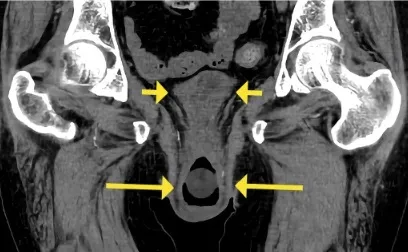

Realizado TC de abdome no 3º dia de internação sendo observado hidronefrose bilateral e prolapso de útero e bexiga (figura 1), o cateter vesical foi identificado dentro do prolapso da bexiga.